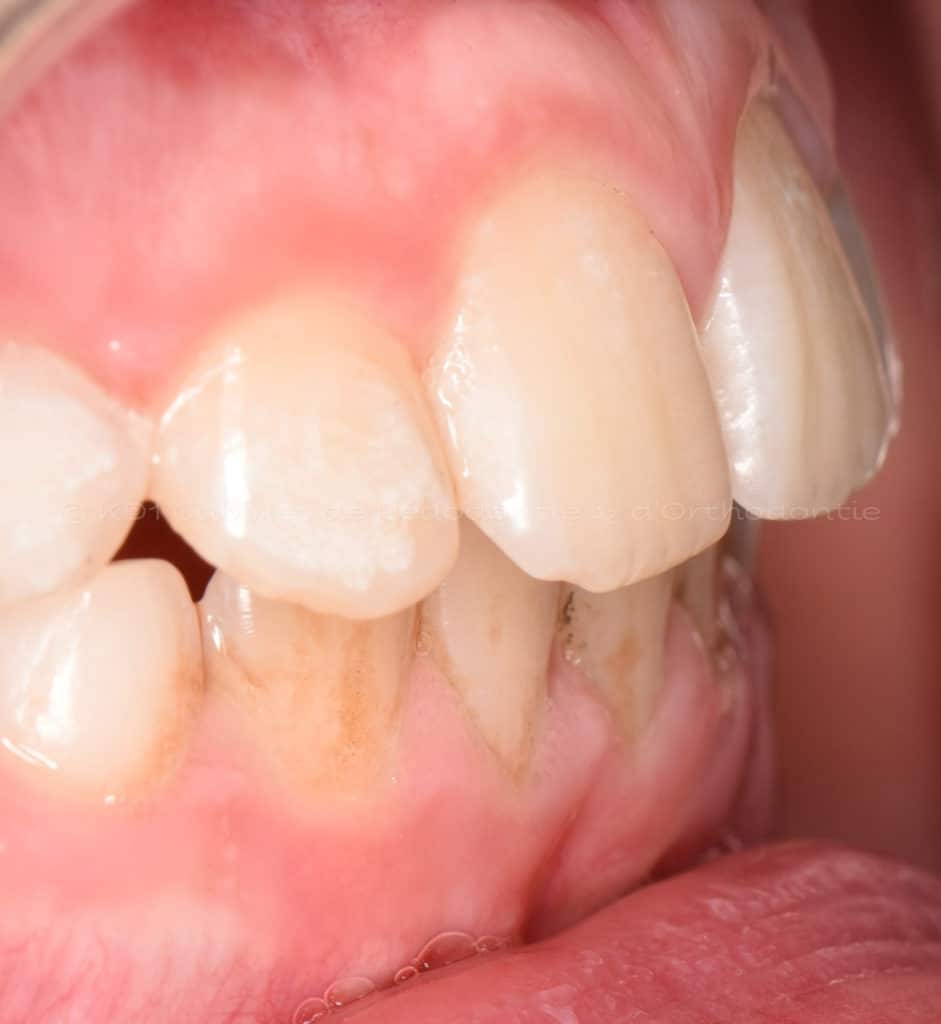

Cas #1 – Traitement avec des bagues, deuxièmes prémolaires et dent de sagesse supérieures ectopiques.